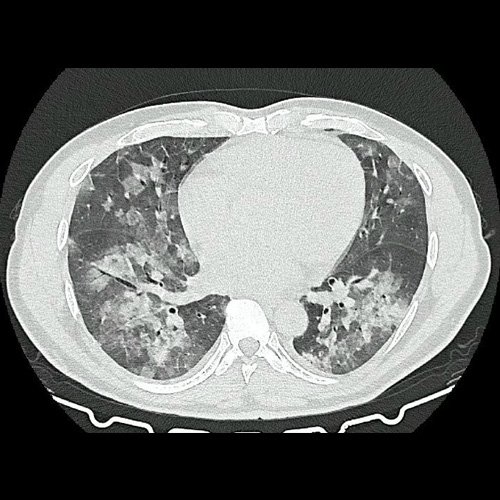

Tomografia de torax sin contraste endovenosos (Ventana pulmonar-corte axial)

• Tomografía de tórax sin contraste endovenoso (Dia 0):Se observan múltiples áreas de consolidación parenquimatosa con broncograma aéreo y de distribución difusa por ambos pulmones, predominando en los lóbulos inferiores, asociadas a engrosamiento de los septos y rodeadas de tenue vidrio esmerilado. Se identifican estructuras ganglionares lateroaórticas, pretraqueales y subcarinales, ninguna de ellas sin alcanzar rango megálico.